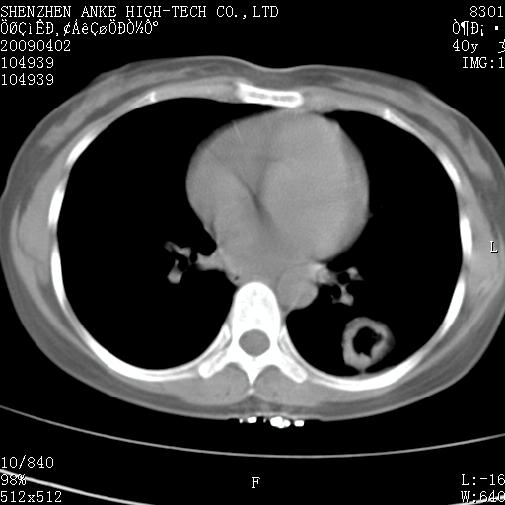

以下是引用随光逐影在2009-4-2 12:16:00的发言:[br]考虑左肺下叶背段继发性肺结核,结核球形成;建议追踪复查。

以下是引用gudu医生在2009-4-2 11:27:00的发言:[br]周围型肺癌

以下是引用卜一在2009-4-2 13:31:00的发言:[br][br] [br] 空洞壁厚不均 胸膜凹陷征。周围型肺癌可能 不排除干酪坏死型肺结核及坏死性肉芽肿。 [br] [br]支持!

以下是引用ct诊断高手在2009-4-2 13:04:00的发言:[br]空洞壁厚不均 胸膜凹陷征。周围型肺癌可能 不排除干酪坏死型肺结核及坏死性肉芽肿。